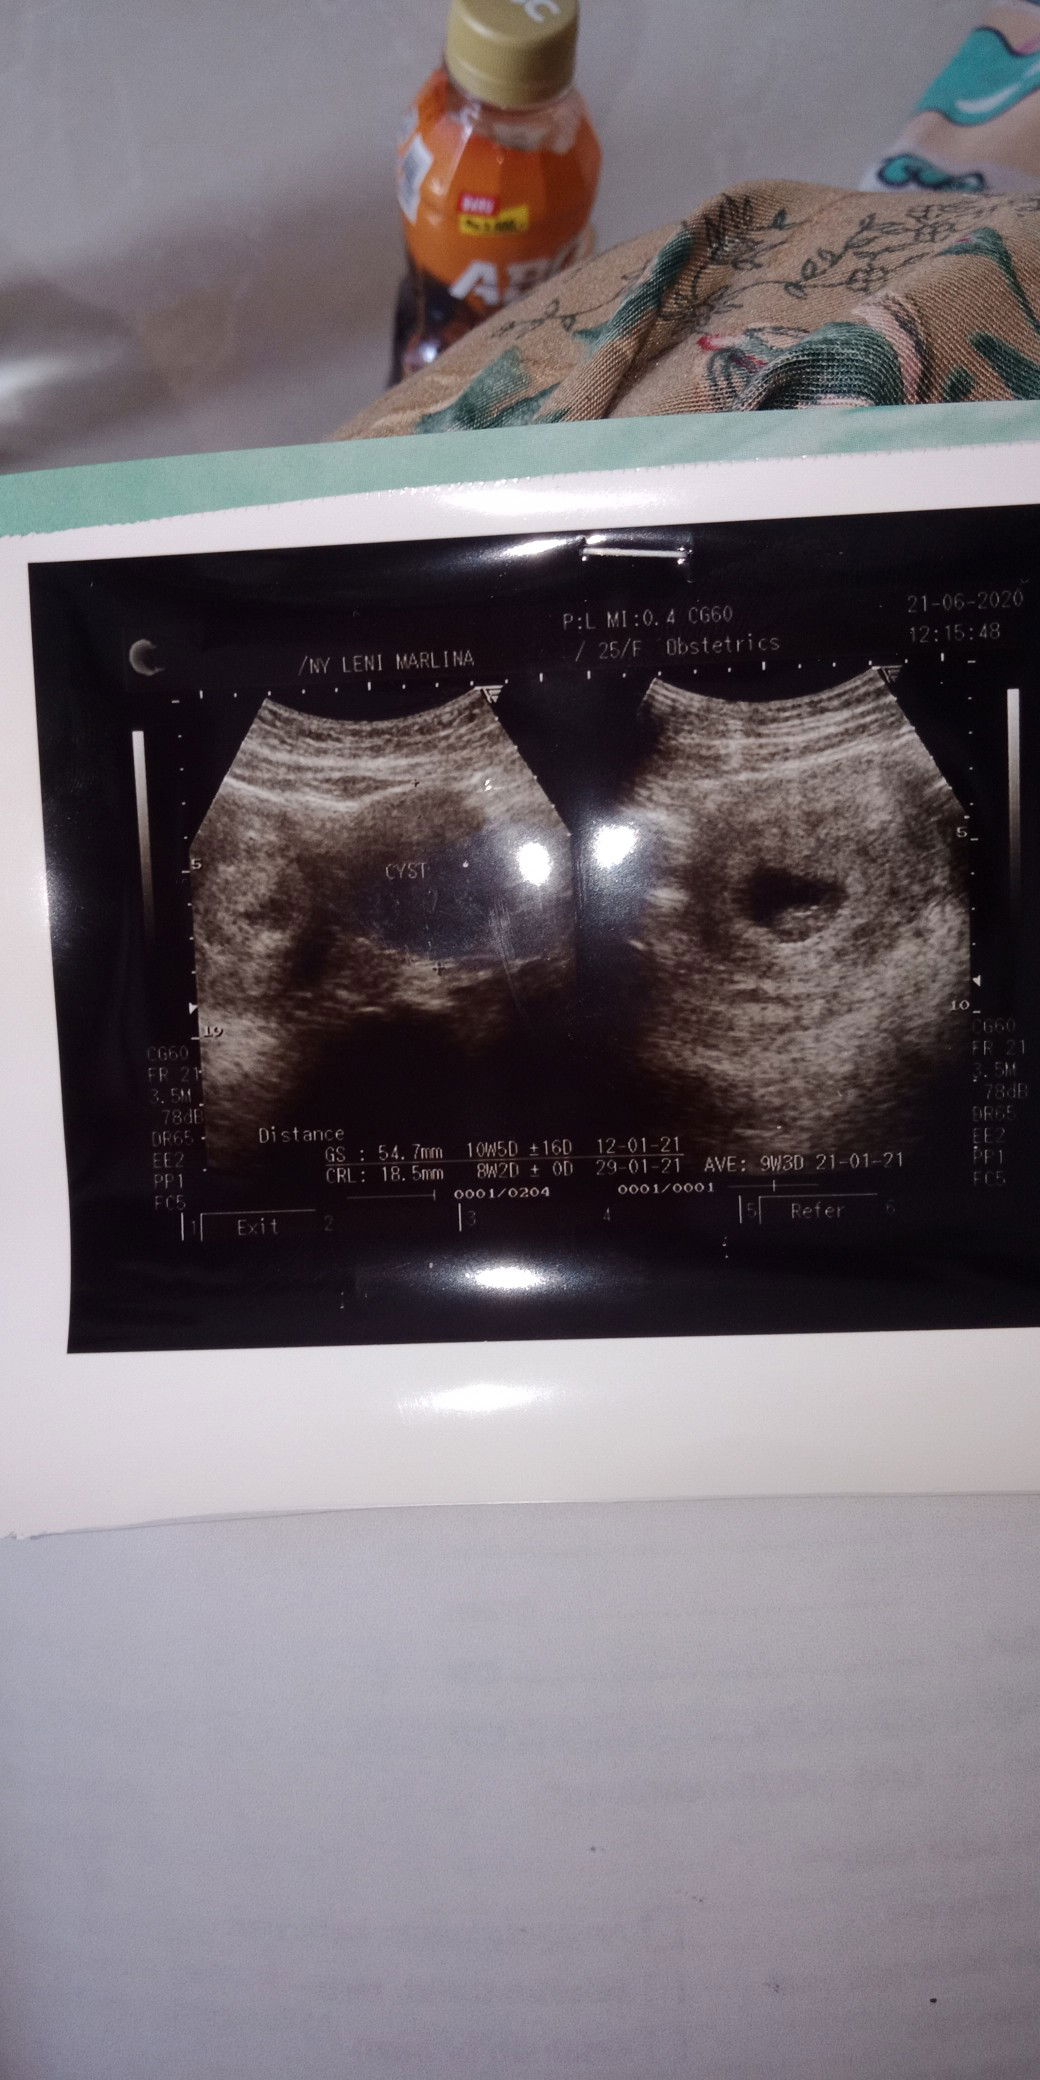

ada kista ovarium di kehamilanku

Bunda mau tanya saya hamil 8 minggu tpi di usg ada kistanya bahaya ngga yah bun. Apa bunda2 di sini ada yg mengalami seperti saya?

Kata dokter ukuran kistanya berapa bun?